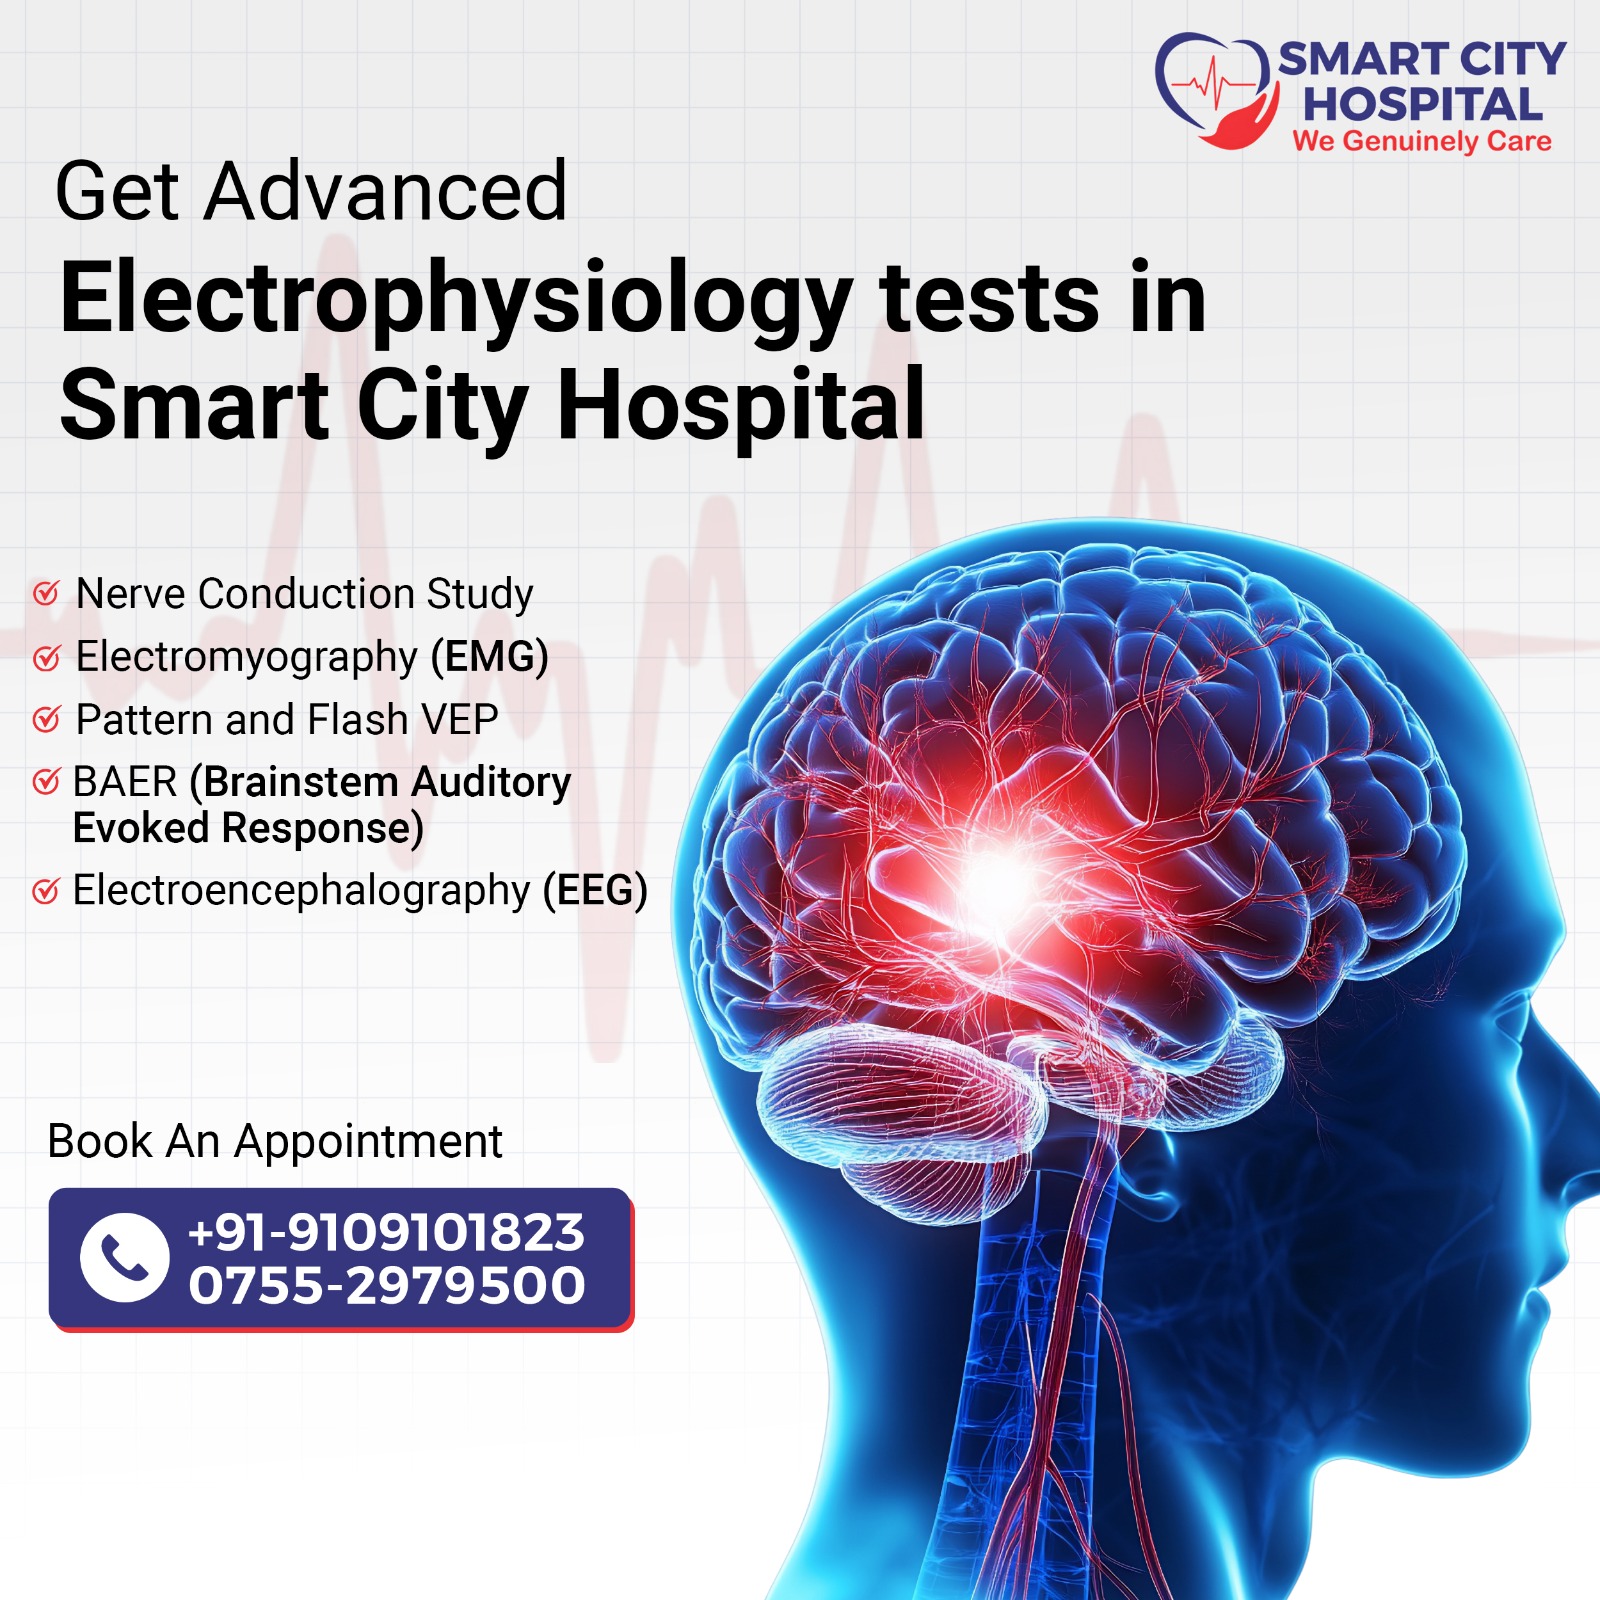

Advanced neurology and neurosurgery services for brain, spine, and nerve disorders, offering cutting-edge treatments and compassionate care for optimal recovery.